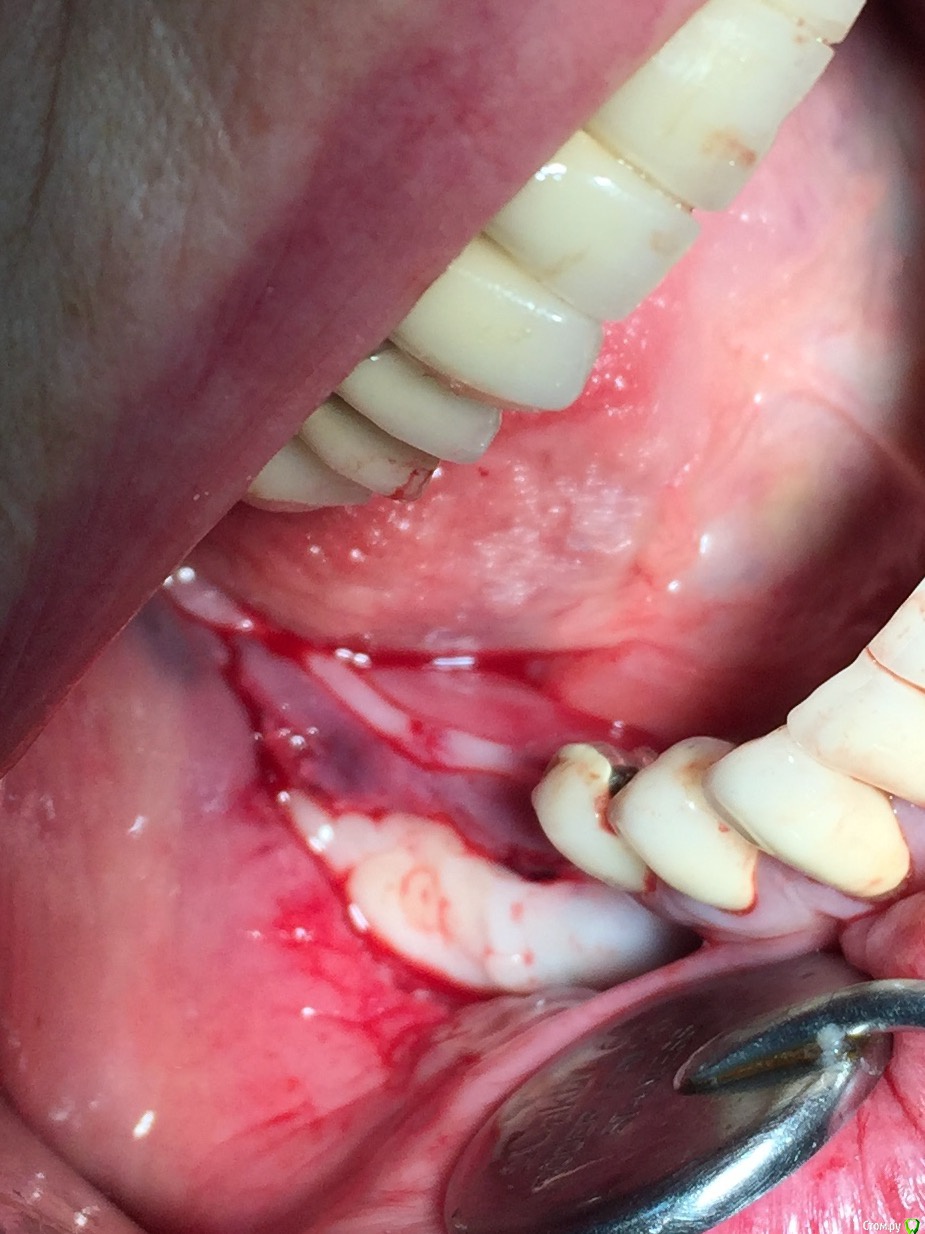

Глеб Митрофанов Опубликовано 22 октября, 2015 Автор Поделиться Опубликовано 22 октября, 2015 круто! а срезы кт есть в этой области? и откуда треугольный ламинат брали, который в щели?Срезы есть , в телефоне найду , прикреплю . Ламинатик получился , путём истончение треснувшей крыши в дистальном отделе , думаю чего добру пропадать , заклинил его и винтом на всякий случай . Ссылка на комментарий

Глеб Митрофанов Опубликовано 23 октября, 2015 Автор Поделиться Опубликовано 23 октября, 2015 Глеб,это вертикальное расщепление. Отлично получилось.Откуда микросом столько нашкрябали?В моём понимании вертикальное расщепление -это классическое расщепление с вертикальным продольным распилом . А стружка с дистальной крыши , который после причесывания микросом превратился в ламинат и с ветви , дистальнее распилов Ссылка на комментарий